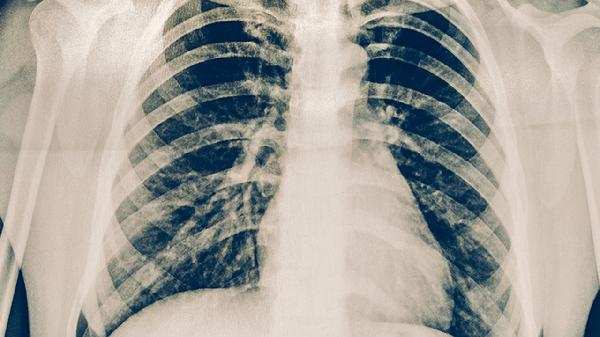

肺结核的规范治疗分为强化期和巩固期两个阶段。强化期一般为2个月,需联合使用异烟肼片、利福平胶囊、吡嗪酰胺片和乙胺丁醇片等药物快速杀灭结核分枝杆菌。巩固期持续4-7个月,通常使用异烟肼片和利福平胶囊维持治疗以防止复发。服药期间可能出现肝功能异常、胃肠道不适、关节痛等药物副作用,需定期复查血常规、肝肾功能及胸部影像学检查。若出现皮肤黄染、持续呕吐或视力下降等严重反应,应立即就医。漏服药物时应及时补服,但不可一次性服用双倍剂量。治疗期间需保持高蛋白饮食,适当补充维生素B6以预防周围神经炎,同时做好呼吸道隔离措施避免传染他人。